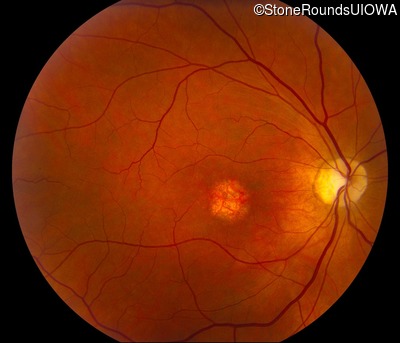

This 59 year old woman first noticed a reduction in her visual acuity and photophobia in her late teens.

| AD Cone and Cone Rod Dystrophy | GUCA1A | Glu155Gly GAG>GGG | AD |

Glu155Gly GAG>GGG